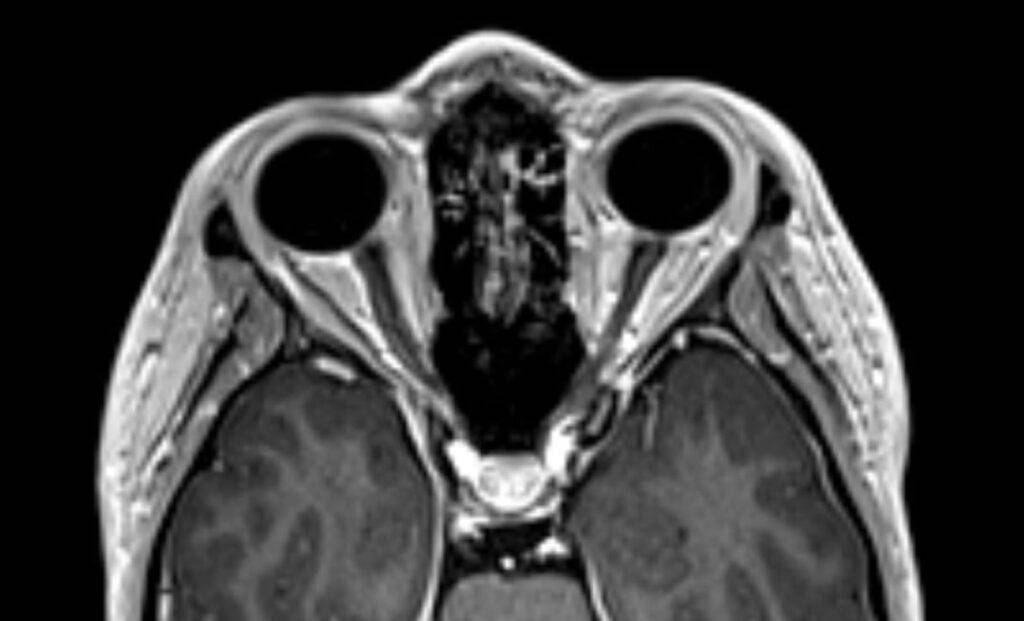

Eine Magnetresonanztomographie des Kopfes, kurz die MRT Kopf genannt, ist ein medizinisch bildgebendes Verfahren. Die MRT Kopf Untersuchung stellt mit Hilfe von Magnetfeldern und Radiowellen insbesondere unser Gehirn, Ohr, Nase und Nasennebenhöhlen, Augen, Kiefer, sowie genaue Strukturen detailliert dar. Vor allem bei diffusen oder langanhaltenden Kopfschmerzen kann eine MRT aufschlussreich sein. Vor allem ermöglicht eine Kopf MRT Einblicke in verschiedene neurologische Erkrankungen.

Eine Kopf MRT liefert Ärzte und Radiologen detaillierte Bilder. Zu sehen sind das Gehirn, Schädelknochen, Blutgefäße und anderer umgebende Gewebe im Kopfbereich.

- Tumore und Zysten: Die MRT Kopf kann sowohl gutartige als auch bösartige Tumore im Gehirn erkennen. Sie kann auch bei der Identifizierung von Zysten und anderen strukturellen Anomalien helfen.

- Schlaganfälle und Blutungen: Auf den MRT-Bildern vom Kopf sind frische Schlaganfälle, Hirnblutungen und andere vaskuläre Probleme im Gehirn zu erkennen.